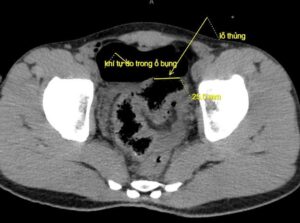

Kết quả chụp X-quang và CT scan ổ bụng cho thấy nhiều khí tự do trong ổ bụng, nghi ngờ thủng tạng rỗng. Bệnh nhân được chỉ định mổ cấp cứu ngay sau đó.

Ê-kíp phẫu thuật tiến hành mổ mở bụng thăm dò, phát hiện ổ bụng có khoảng 100ml máu và dịch bẩn. Đại tràng sigma có đoạn tổn thương dài 5cm, lỗ thủng khoảng 2cm, xung quanh dập nát.